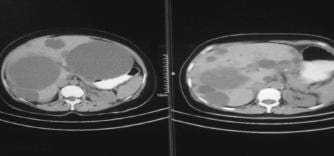

En el control de tomografía (figura 4) se observó la persistencia de un quiste gigante, que no se drenó en el primer acto por estar localizado centralmente. Se programó para su aspiración y esclerosis, dada la localización y la necesidad de preservar la mayor cantidad posible de tejido hepático ante la alteración de las pruebas hepáticas presente desde antes de la cirugía y motivados por la mejoría clínica en consulta externa, donde la paciente refirió disminución absoluta del dolor y tolerancia normal de la dieta; además, en la palpación del abdomen no había sensación de masa, como sí se encontró antes de la intervención quirúrgica.

FIGURA 4. Corte tomográfico antes (izquierda) y después de la resección del techo del quiste (derecha), con imagen de quiste central no resecado inicialmente.